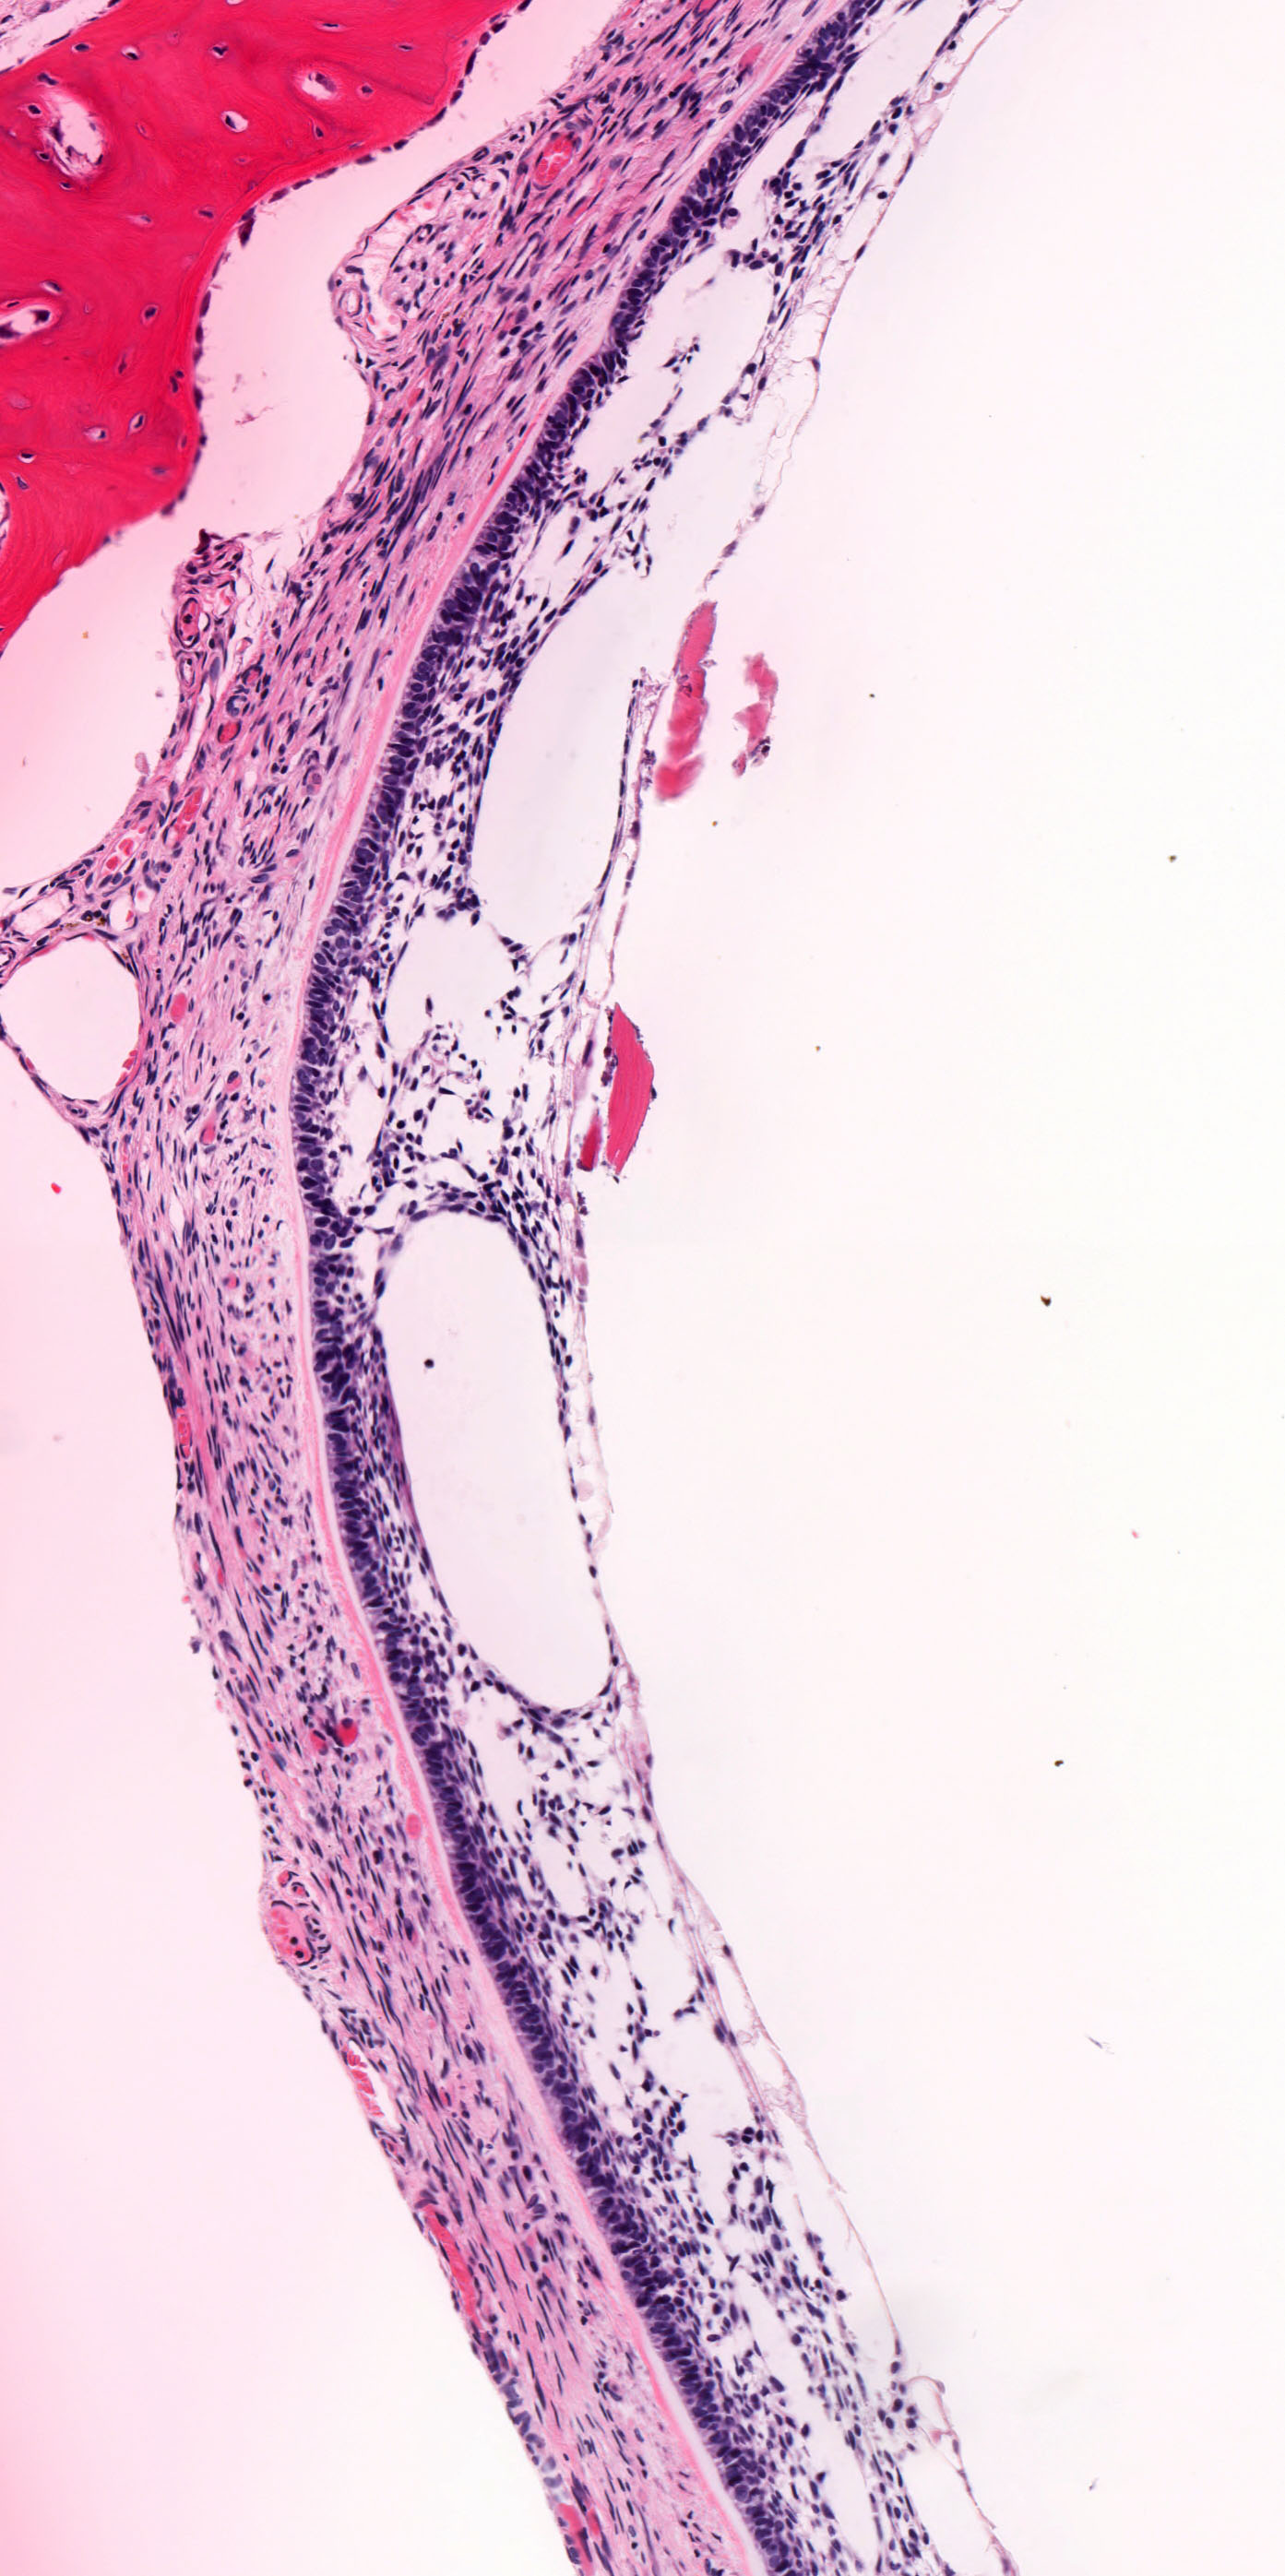

Microscopic (histologic) images

Contributed by Kelly Magliocca, D.D.S., M.P.H. and Anne C. McLean-Holden, D.M.D., M.S.

- Ameloblastoma, unicystic type has 3 histopathological patterns

- Single cystic lesion lined by ameloblastic epithelium that shows typical features of ameloblastoma in some areas, including columnar basal cells in palisading arrangement with vacuolated cytoplasm, hyperchromatic nuclei polarized away from basement membrane

- Suprabasal cells loosely textured and noncohesive resembling stellate reticulum, epithelial invagination, epithelial edema and separation

- Microscopic variants (may result in treatment differences - controversial)

- Luminal: cystic odontgenic epithelium with characteristic features (above) lining fibrous connective tissue wall

- Intraluminal: cystic odontgenic epithelium with characteristic features (above) lining fibrous connective tissue wall, with tumor extending into the cystic luminal space; may have intraluminal plexiform patterns

- Mural: cystic odontgenic epithelium with characteristic features (above) lining fibrous connective tissue wall but with the additional finding of definite ameloblastoma tumor islands within the fibrous connective tissue wall

- Within the epithelial islands and cords of conventional ameloblastoma and the cystic epithelial lining of unicystic ameloblastoma, the odontogenic epithelium shows similar changes:

- Columnar cells with hyperchromatic nuclei at basal layer, exhibiting peripheral palisading

- Cells show reverse polarization away from basement membrane (Vickers-Gorlin change)

- Subnuclear vacuolization

- Suprabasal cells with a loose, network-like arrangement, recapitulating stellate reticulum formation seen in normal odontogenesis